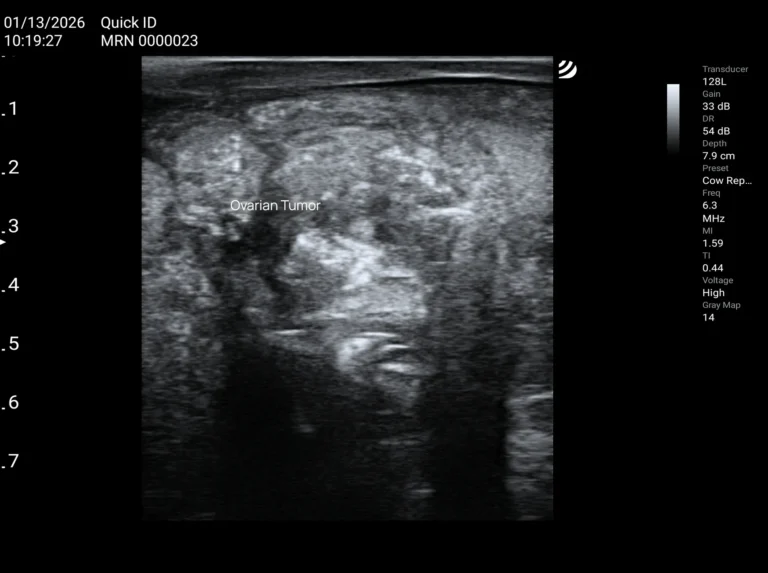

Read moreOvarian and Uterine Tumors in Cows

Various abnormalities and pathological changes can occur in the reproductive system of cows. They affect the animal’s overall health, fertility, and the course of the estrous cycle—among others, through disturbances in prostaglandin secretion and, consequently, the lack of luteolysis of the corpus luteum. These changes may have a hormonal background or result from mechanical injuries. […]